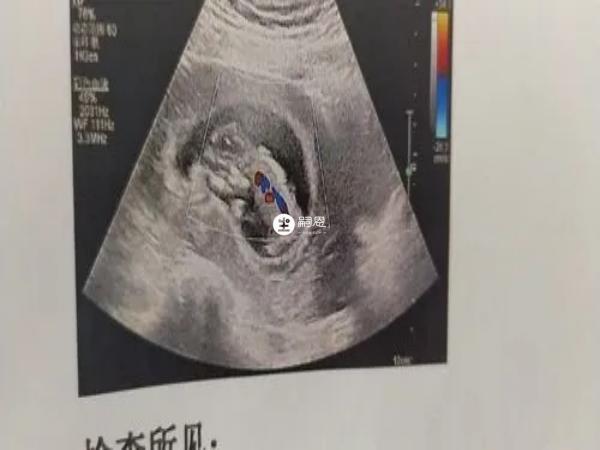

民間有B超影象看男女的說法,並且有很多已經分娩的寶媽表示準確率很高,其實這些都是過來人的經驗總結,並沒有科學依據,據說B超影象上懷女寶和男寶的性別特徵不一樣,有人認為當影象上胎兒雙腿之間區域出現三條白線時,表示可能懷女孩,如果出現三個亮點,表示可能懷男孩,具體如下:

在網路上流傳著B超影象看男女的說法,該方法主要是通過觀察超聲影象上,是否出現三條線為判斷依據,因為如果B超影象上出現三條白線,代表該區域是懷女寶的性別特徵,說明可能懷女孩,可以判斷孕婦生女寶寶的可能性較大。

其實按照B超影象看男女的方法,如果是懷男寶寶的話,影象上是不會出現三條白線的,因為那是懷女孩的性別特徵,如果是懷男孩的話,B超影象上應該出現三個亮點,通常代表男孩的性別特徵,因此準媽媽在B超影象上通過觀察發現,在雙腿之間的區域有三個亮點的話,那麼懷男孩的可能性更大。